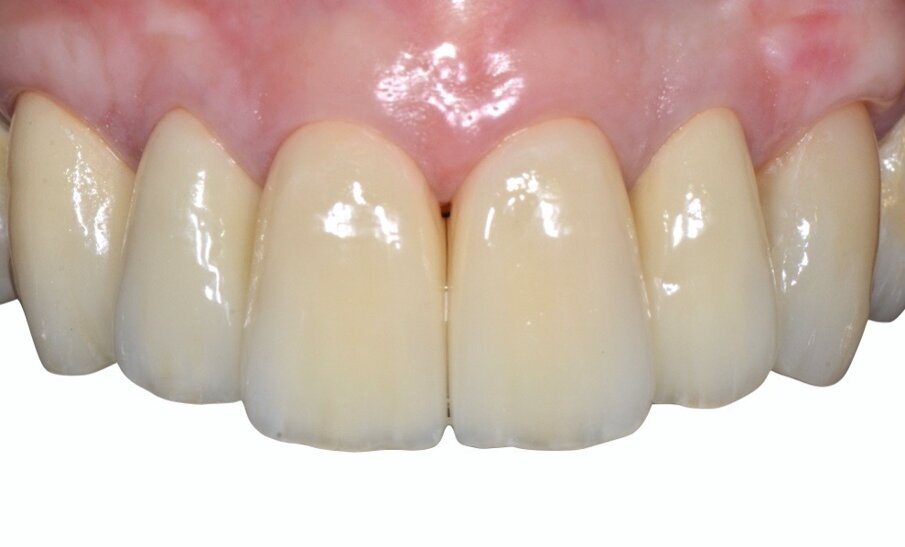

Da un punto di vista protesico verranno eseguite corone singole in zirconia stratificata sugli elementi 13-12-11-21-22 e una faccetta in disilicato di litio sul 23. A causa della notevole rotazione dei due incisivi centrali in fase di ceratura abbiamo optato per due corone complete anziché due faccette per una migliore distribuzione degli spazi protesici dei quattro incisivi (Fig. 8). Il gruppo frontale inferiore invece verrà protesizzato con corone in zirconia stratificata sugli elementi 32-31-41-42-43 splintate per compensare una mobilità di grado 1 dei quattro incisivi.

Inizialmente vengono applicati i provvisori prelimatura (Fig. 9) utilizzati anche come mock-up per passare dopo le opportune valutazioni estetiche (Figg. 10, 11) a una seconda serie di provvisori che ci accompagnaranno durante la fase chirurgica e il tempo di guarigione e maturazione dei tessuti. Prima si procede con la chirurgia resettiva (ORS) sul canino superiore destro per alzare la parabola gengivale a livello degli altri denti frontali; questo intervento viene eseguito con un approccio “delicato” e meno invasivo possibile per non penalizzare l’estetica della corona preesistente sul primo premolare superiore destro.